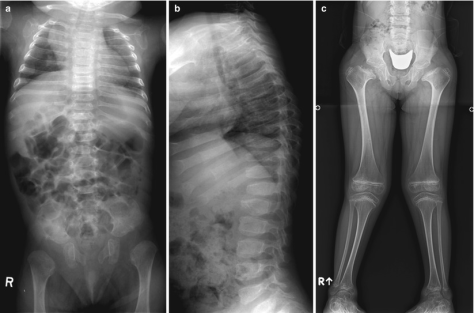

Fig.1. a,b) Radiografias da coluna vertebral de uma menina de 8 meses mostram vértebras planas com cunha anterior. ilíacas curtas e epífises proximais não são ossificadas. (c) vista anteroposterior de uma rapariga de 7 meses mostra um colo femoral largo e curto e uma ossificação atrasada da cabeça femoral. As epífises no joelho são grandes e a placa de crescimento da tíbia tem forma de V invertido. Créditos: Radiology Key